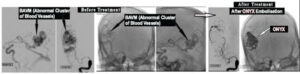

Embolisation of Brain Arteriovenous Malformation, BAVM (Abnormal cluster of blood vessels in Brain) :

Example:45 Yrs. old gentleman presented with severe headache &Lt.; side paralysis due to Brain hemorrhage from Brain AVM. After ONYX Embolisation of Brain AVM ,he recovered completely.